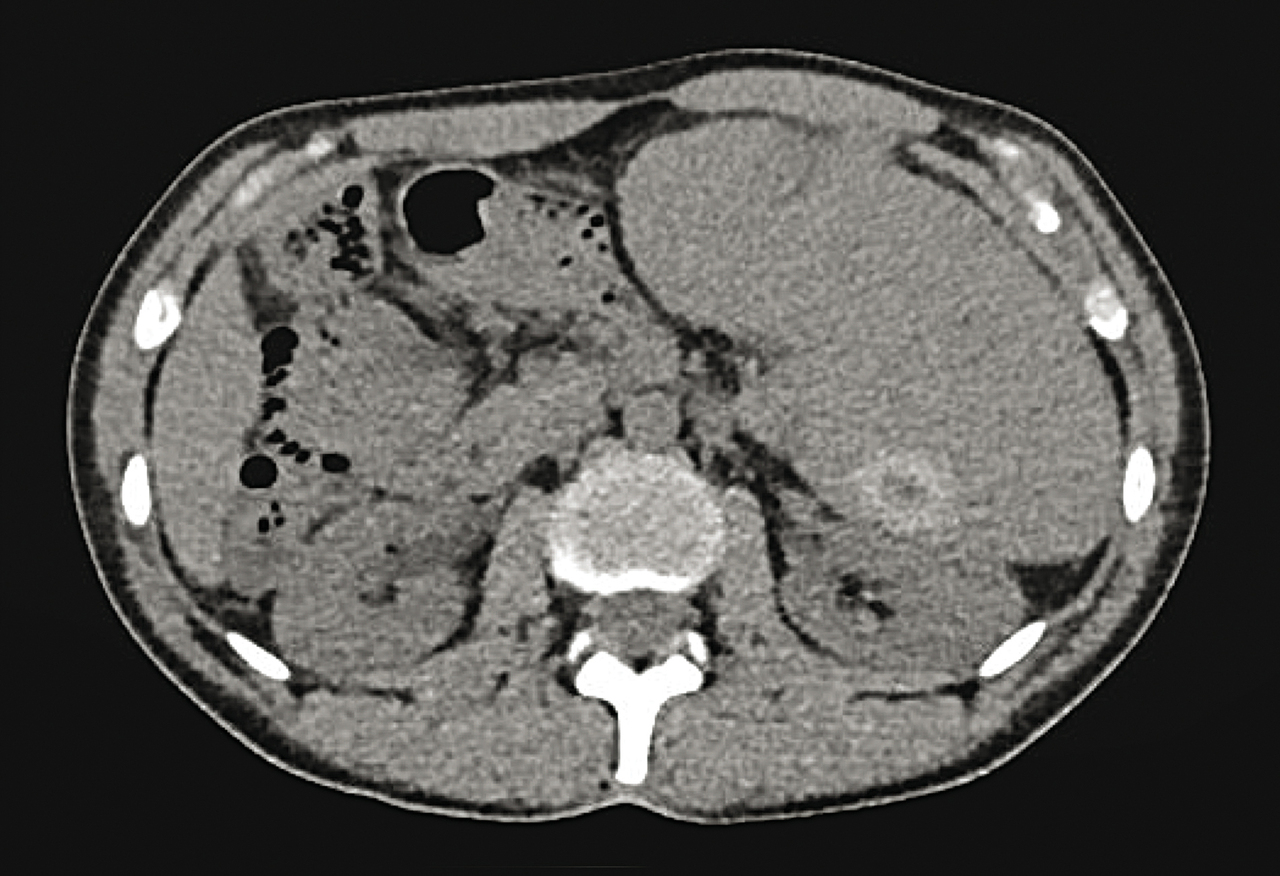

Quel est votre diagnostic ? Lymphome splénique Sarcoïdose Leucémie myéloïde chronique Maladie de Waldenström Angiosarcome splénique Il s'agit d'un angiosarcome splénique. Pour en savoir plus : - Bastie JN. Splénomégalie. Rev Prat 2010;60(4): spécial web. OK Valider mes réponses